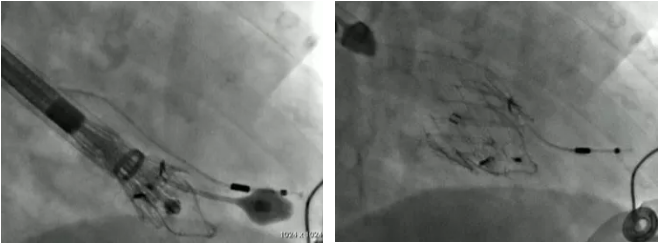

图2:Anson Cheung及John G Webb教授团队手术过程

图1:Anson Cheung及John G Webb教授团队手术过程(安贞医院张海波教授作为中方医疗专家,代表长海医院徐志云、陆方林教授团队参与手术)